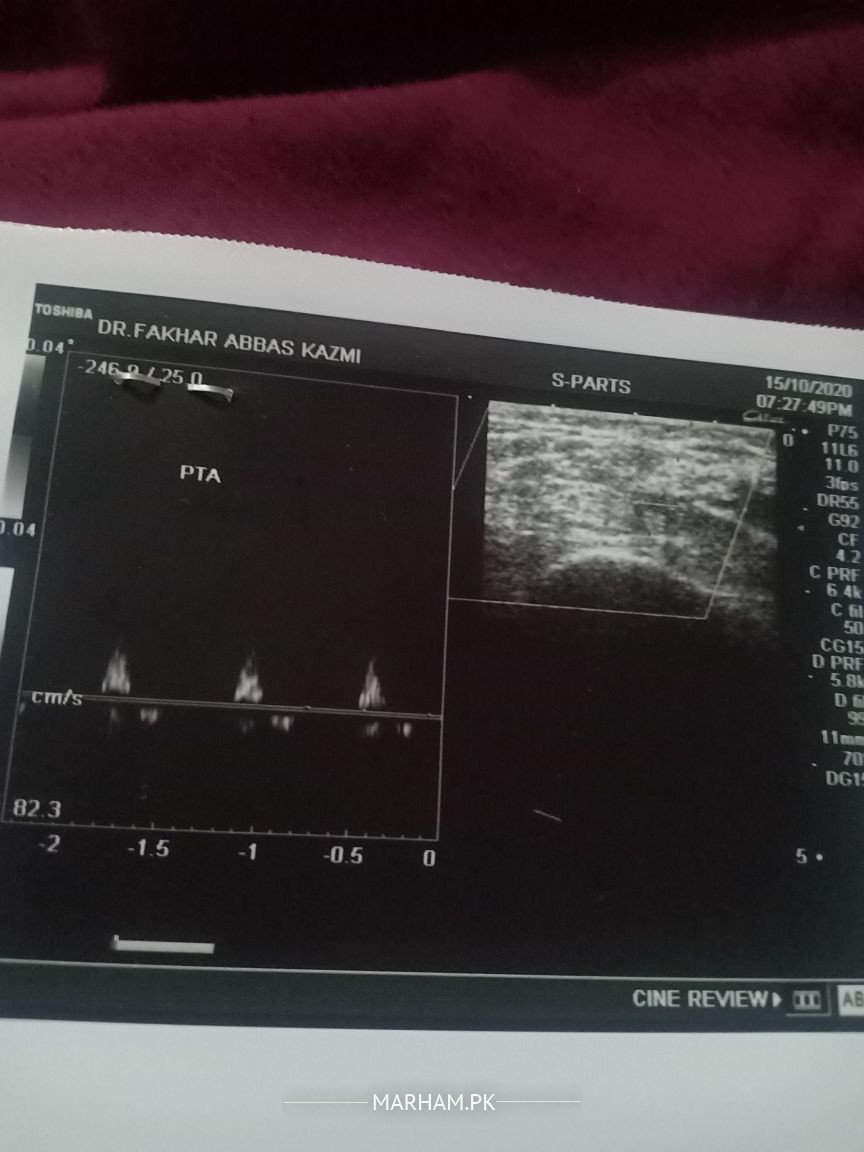

mohtaram Docter sahiban AoA. Moderately sever peripheral vascular diease in bilateral lower limbs with changes more marked on right side. ye ultrasound ka result hy .legs mn shadeed pain hota hy .shugar b hy .reports attach hn .plz rahnumai farmaen k kis dr sy treatmint kerwana chahye . mn ap ko reports or jo hn medecien ly rahy hn wo b send kr raha hn ye meri wife ko problem hy .Thanx

dear patient, you have deceased vessels due to your diabetes.

pl book appointment for consultation.

you may need further tests to guide u to proper treatment.